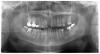

Jul Опубликовано 30 сентября, 2008 Поделиться Опубликовано 30 сентября, 2008 Здравствуйте, уважаемые стоматологиПомогите, пожалуйста, советом. Неделю назад удален 11, была киста.Можно ли поставить имплант или придется делать мост? Буду очень благодарна за рекомендации Ссылка на комментарий

Bier Опубликовано 30 сентября, 2008 Поделиться Опубликовано 30 сентября, 2008 По высоте костной ткани достаточно, а ширины по снимку не видноНужна очная консультация.Но так или иначе - здоровому человеку имплантат можно поставить всегда Ссылка на комментарий